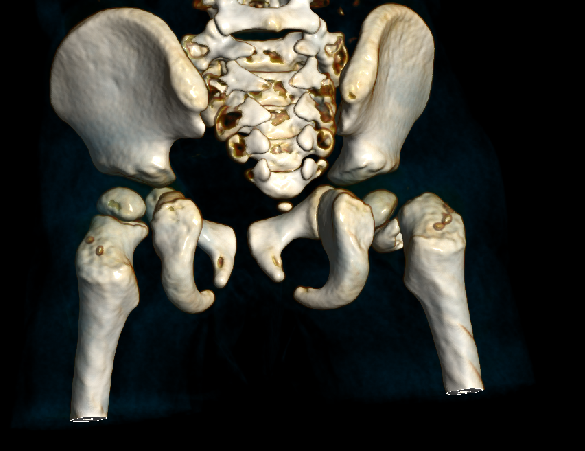

患 者:邱某,男,79岁。

主 诉:因撞伤致左髋部疼痛、活动受限30分钟,入院治疗。

症 见:患者自诉被小货车撞伤,致左髋部肿痛伴活动受限,受伤当时患者无昏迷、晕厥,无恶心、呕吐,无胸闷、气促,受伤后来入院就诊。

查 体:T:36.7℃,P:52次/分,R:20次/分,BP:130/74mmHg。

专科检查:神志清楚,检查合作,左髋部稍肿胀,皮肤粘膜完整,局部皮色淤青,左下肢外旋、未见明显短缩,左髋局部压痛,左足底叩击痛,左髋关节主动伸屈、外展、内收等活动受限;左下肢末梢皮色红润,感觉良好。

影像资料:

骨盆正位

髋部CT

髋部CT+骨三维

诊 断:

左股骨粗隆骨折,伴心动过缓,三度房室传导阻滞。阿托品试验阴性。